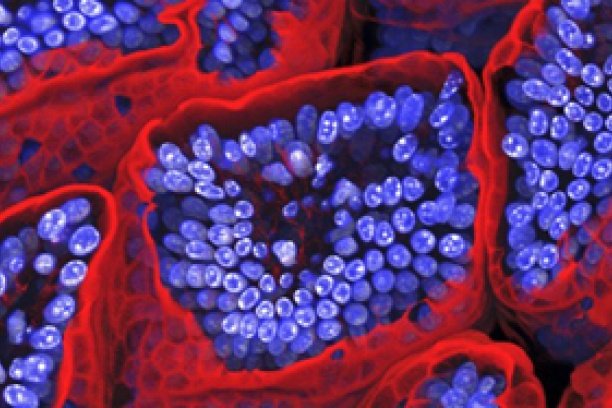

Our bodily organs are lined by sheets of polarizing epithelial cells that provide a vital layer of protection against noxious agents in our external and internal environment. Mutations in epithelial cells result in carcinomas that make up more than 90% of all cancers.

The EBC brings together investigators from multiple disciplines to address complex issues related to the physiology and pathophysiology of epithelial cells. Major areas of investigation include establishment and maintenance of epithelial cell polarity, regulation of vesicle trafficking and cytoskeletal organization, epithelial defense against infectious agents and the identification and characterization of adult epithelial stem cell populations.